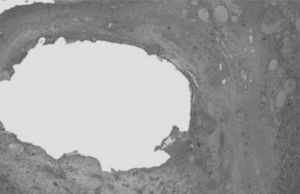

ResultadosEl estudio incluyó a 116 pacientes, 98 (84,4%) asintomáticos y 18 (15,5%) con clínica relacionada con la malformación pulmonar y manifestada antes de la cirugía. En este grupo, 10 pacientes (55,5%) presentaron sintomatología de tipo infeccioso y 8 clínica de dificultad respiratoria (2 pacientes con ventilación mecánica, 3 con soporte no invasivo tipo CPAP y 3 con oxigenoterapia). Las niñas presentaron clínica con mayor frecuencia que los varones en nuestro estudio (p=0,040) y la localización más frecuente fue en los lóbulos pulmonares inferiores (78,4%) (fig. 1). El tipo histológico más común fue el correspondiente a MCVAP (35,5%) seguido de secuestro intralobar (27,3%) y secuestro extralobar (11,8%) (fig. 2). Focalizando en los pacientes sintomáticos la distribución histológica fue la siguiente: MCVAP (9 casos), secuestro intralobar4, secuestro extralobar2, hiperinsuflación lobar congénita2 y blastoma pleuropulmonar1 (fig. 3). Considerando las variables analizadas en ambas cohortes de pacientes, sintomáticos y no sintomáticos, hemos detectado que el tamaño de la lesión en la TC fue significativamente más grande en el grupo de pacientes que desarrollaron sintomatología (p=0,027) (fig. 4). Aunque no alcanzó significación estadística, el desplazamiento mediastínico en la ecografía prenatal de los pacientes sintomáticos fue también más frecuente. Con respecto al eventual impacto de la presencia de clínica previa en el curso intra y postoperatorio, la tasa de conversión a cirugía abierta fue mayor en los pacientes sintomáticos sin repercutir de una manera significativa en la duración de la estancia hospitalaria (tabla 1). Por otra parte, no se identificaron un mayor número de complicaciones postoperatorias en el grupo de pacientes con síntomas previos (tabla 1). Los tipos de complicaciones recogidas en nuestro estudio fueron: sangrado, fuga aérea persistente, enfisema subcutáneo severo, fiebre mantenida y sepsis.

Mientras que hay un consenso generalizado en cuanto a la necesidad de resección quirúrgica en los pacientes con MPC que presentan clínica respiratoria o infecciosa, existe disparidad de criterios cuando el curso es asintomático7–11. Esta falta de consenso es todavía más acusada cuando se trata de establecer el momento óptimo para la exéresis quirúrgica de la lesión. Aunque el desarrollo reciente de técnicas de CMI ha permitido la realización de resecciones pulmonares con seguridad en los pacientes cada vez más pequeños, el momento ideal para la cirugía está todavía por definir. Diversos autores han comparado los resultados quirúrgicos obtenidos en los pacientes asintomáticos pertenecientes a diferentes grupos de edad, siempre por debajo del año de vida, no habiendo encontrando diferencias significativas en cuanto al curso postoperatorio y la aparición de complicaciones4,13. Por otra parte, también se ha investigado sobre el eventual impacto de la presencia de sintomatología preoperatoria en los resultados posquirúrgicos. Aspirot et al.25 demostraron un aumento significativo de las complicaciones postoperatorias y estancia hospitalaria en los casos con clínica previa. Sin embargo, otros autores no han detectado un impacto relevante en este sentido21,26. En nuestro estudio no se evidenció un aumento significativo de las complicaciones postoperatorias en los pacientes con sintomatología previa, pero si existió una mayor tasa de conversión por dificultades técnicas en este grupo, sin un incremento significativo del tiempo quirúrgico. Con frecuencia, los pacientes que han sufrido una neumonía previa en el lóbulo donde asienta la lesión exhiben adherencias tisulares y adenopatías cisurales en la cirugía. Esto implica una disección más dificultosa, lenta y con más riesgo de sangrado, que eventualmente puede modificar el abordaje inicial y convertirlo en una cirugía abierta, como ocurrió en 2 pacientes de nuestra serie27,28. Dado que la sobreinfección de las MPC puede oscilar entre el 10 y el 30% en el primer año de vida, diversos autores recomiendan la exéresis quirúrgica de la lesión durante este periodo para evitar eventuales procesos infecciosos que puedan comprometer el resultado esperado de un abordaje mínimamente invasivo5,13,18,29,30. Aunque con nuestra casuística no se puede establecer una significación estadística, sí se podría inferir que con una muestra mayor una intervención precoz probablemente tendría un impacto positivo en el índice de conversión a cirugía abierta. Otro argumento a favor de la cirugía precoz radica en la posible transformación maligna de algunas MCP y más concretamente de las MCVAP31. No existe una evidencia clara sobre si el tumor ya existe desde el principio o se produce una transformación histológica de las lesiones quísticas, pero en cualquier caso, la incidencia es muy baja21. En nuestra serie, solo un paciente presentó una histología maligna tipo BPP lo que representa una tasa del 0,86% que está en sintonía con las publicadas por otros grupos13,32.